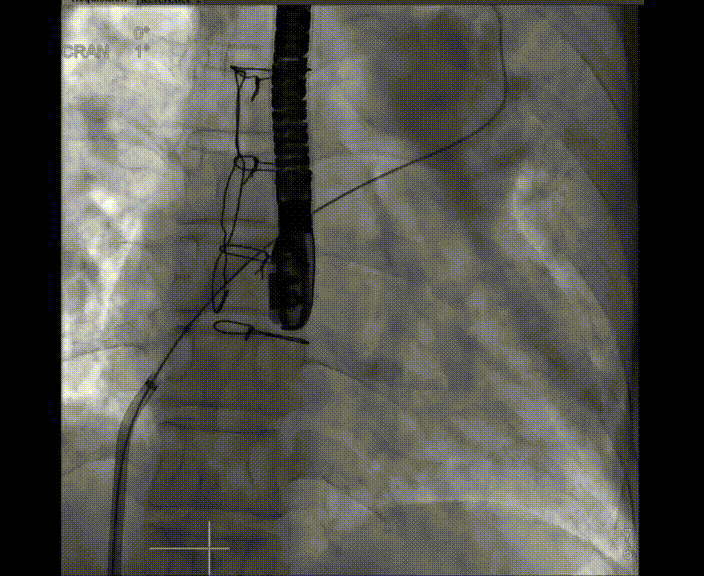

術(shù)中首先在局麻下穿刺股動脈、股靜脈,完成心導(dǎo)管檢查評估后轉(zhuǎn)為全麻,在食道超聲引導(dǎo)下穿刺房間隔,穿刺成功后將加硬導(dǎo)絲送入左上肺靜脈建立軌道,根據(jù)患者病情行球囊預(yù)擴(kuò)張后植入6mm孔徑房間隔造孔支架,經(jīng)透視及食道超聲評估支架左右盤展開良好,夾持于房間隔兩側(cè),固定穩(wěn)定、位置良好,食道彩超顯示房水平右向左為主分流,分流孔直徑符合預(yù)期大小,心導(dǎo)管檢查評估達(dá)到預(yù)期效果,釋放造孔支架。術(shù)后12h患者下床活動,恢復(fù)順利,擬于近日完善術(shù)后評估后出院。